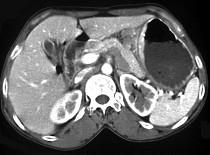

问题 女,56岁,上腹部钝痛、腹胀不适1月余,纳差、消瘦,影像检查如图,最可能的诊断是 ( )

选项 A.胃幽门管溃疡 B.胃腺癌并幽门狭窄 C.胃淋巴瘤 D.胃间质瘤 E.胃恶性间质瘤

答案 B